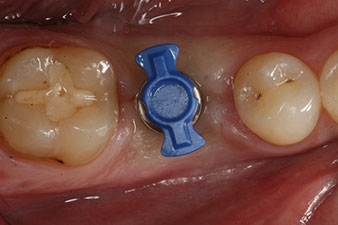

SmartPeg

Abb. 4: Eingeschraubter SmartPeg Messpfosten für die Bestimmung des Implantatstabilitäts-Quotienten mit dem integrierten W&H Osstell ISQ Modul.

Das Drehmoment beim maschinellen Einbringen war 43 Ncm. Zusätzlich wurde, nach Einschrauben eines speziellen, auf das Implantatsystem abgestimmten Mess-Pfostens (SmartPeg), der ISQ-Wert mit der Sonde des W&H Osstell ISQ Modul bestimmt.

Dieses Modul ist für das Implantmed von W&H optional erhältlich und wird an den Implantologiemotor gedockt (vgl. Abb. 11). Der dimensionslose ISQ-Wert war direkt bei der Insertion 64 in oro-vestibulärer und 68 in mesio-distaler Richtung (Maximalwert = 100). Dies hätte eine offene Einheilung oder sogar Sofortversorgung erlaubt.